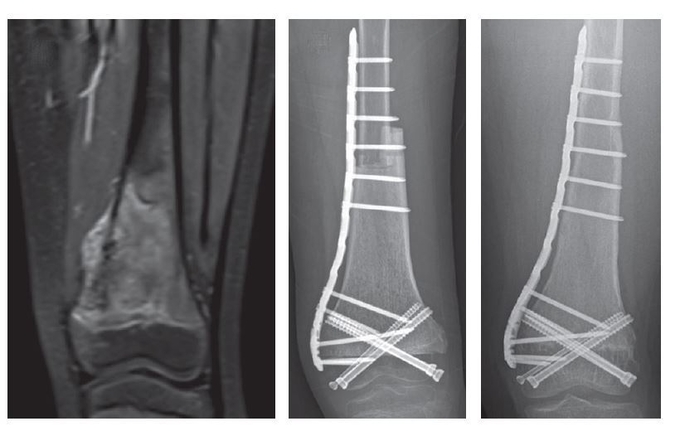

수술 직후(가운데)와 수술 후 4년 이후(오른쪽) 환자의 단순방사선사진. 종양을 제거한 부위는 골이식을 통해 개건했다. 해당 환자의 무릎관절운동은 완벽하게 정상수준까지 회복됐다.

이때 연구팀은 수술 전 항암치료효과가 좋은 환자를 대상으로, 관절을 구성하는 뼈 부분은 보존하면서도 종양이 있는 뼈 부분만 제거했다. 종양이 있던 위치는 조직기증으로 확보한 타인의 뼈를 이식해 개건했다.

이는 기존 방식보다 수술 효과, 움직임, 합병증 위험에서 월등하게 우수했다. 우선, 수술을 받은 17명의 환자를 최대 10년 이상 관찰한 결과, 수술 부위에서 골육종이 재발한 환자가 없었다.